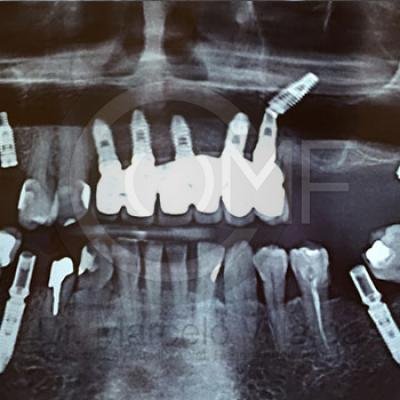

Implante en Seno Maxilar